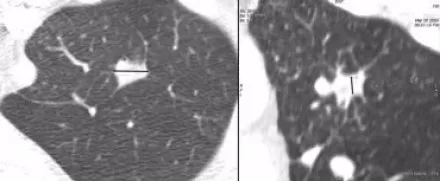

图3 左图为横断面图像,右图为冠状重建图像

计算三维比率需要两个径线,即上图结节中的黑色直线:最大横径(左)和最大垂直径(右)。三维比值 = 最大横径/最大垂直径。

三维比值越大,说明病灶相对平坦、非块状,考虑良性的可能性也越大。